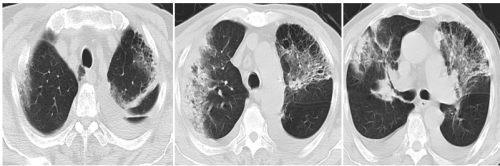

转归:10.11日复查肺ct:与5日肺ct比较 炎症病灶有吸收,双侧胸腔积液增多(考虑与低蛋白血症有关)。10.12日出院后继续口服莫西沙星2周,甲泼尼龙片2周(逐渐减量)。症状明显好转,可下床活动。

10.11肺ct 如下